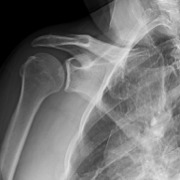

This 48-year-old male is a right hand dominant, nonsmoker with an active lifestyle. This patient presented with excellent range of motion and passing inactive range. Upon examination, strength presented at 5/5 rotator cuff, mild tenderness over the proximal long head of the biceps, but positive for subacromial impingement testing. Imaging revealed a skeletally mature individual with an intact glenohumeral joint space without signs of osteoarthritis and an intact acromial-humeral height distance (Figures 1-3).